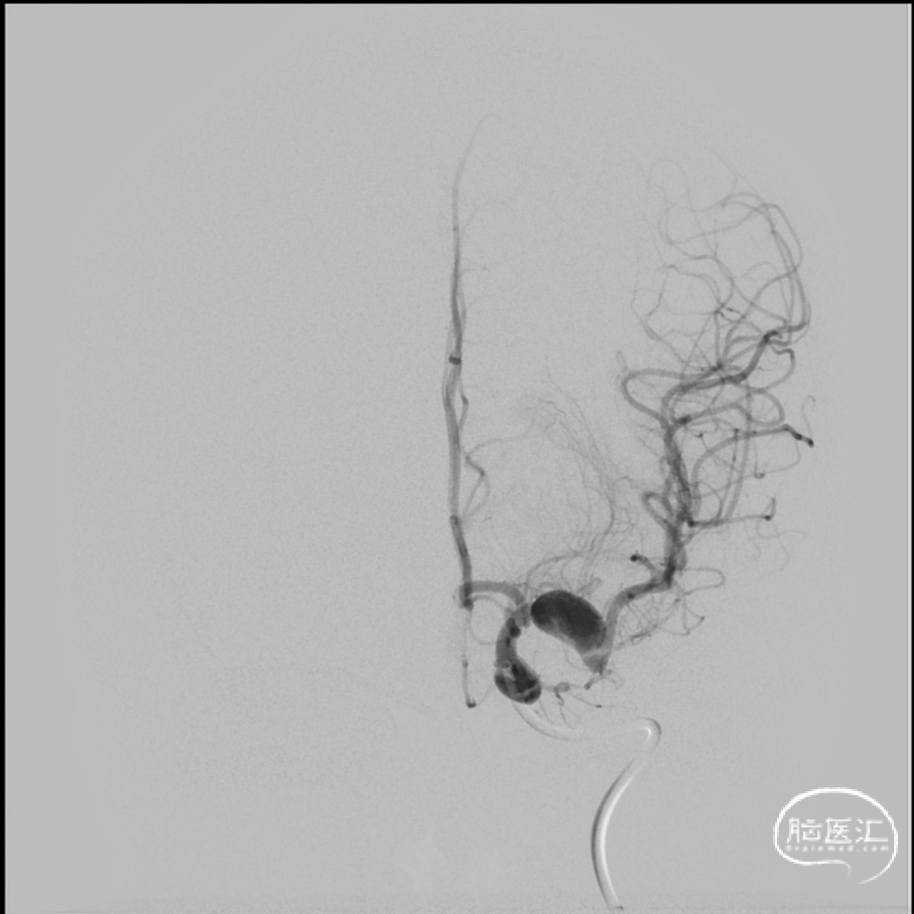

2024年4月1日 DSA

L ICA

L ICA 3D

AN长径9.14mm

远端血管大脑中直径2.34mm、近端颈内末端4.25mm

手术过程

L ICA

Pre-OP

Post-OP